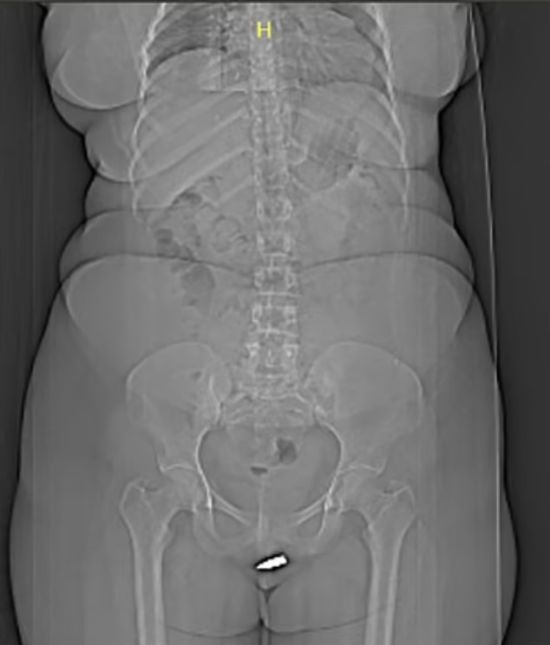

Женское обрезание. 200 млн девушек от Америки до Африки искалеченные ужасной традицией – ООН

Увечье половых органов приводит к серьезным проблемам со здоровьем, в частности - психическим. ru.tsn.ua »